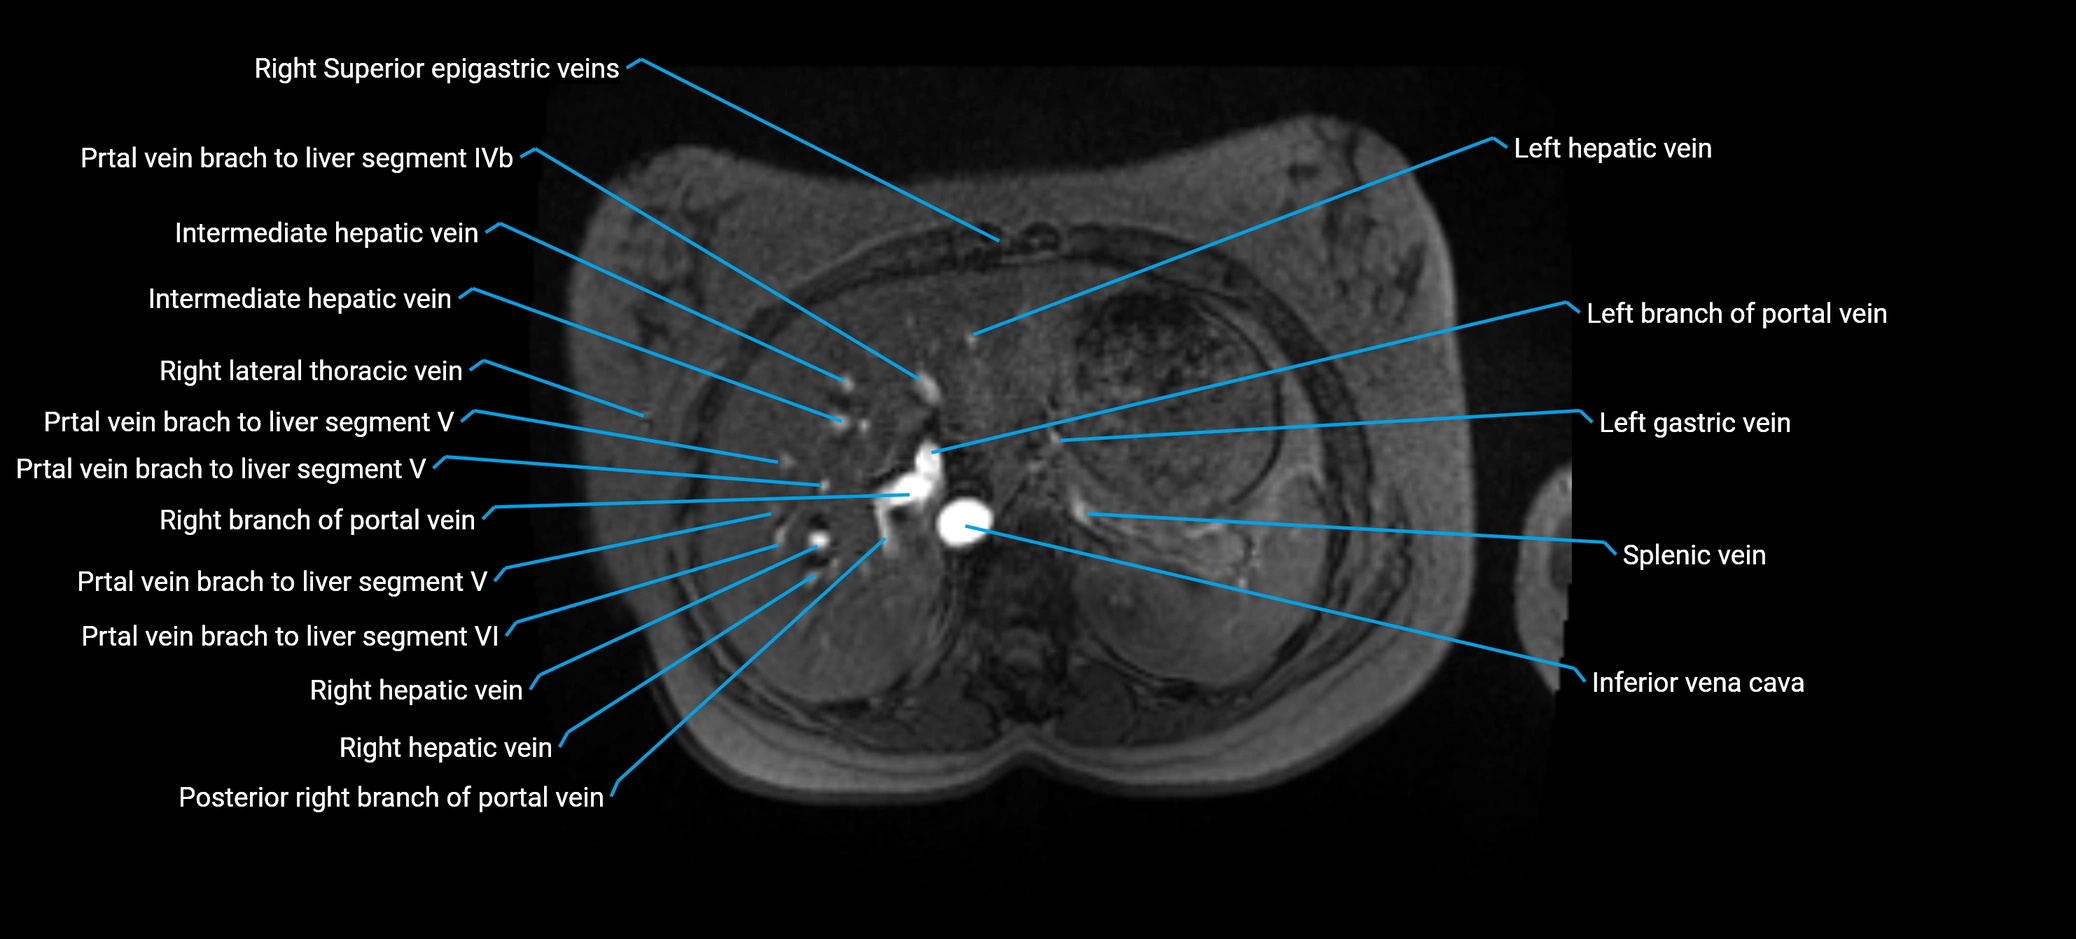

The anterior right branch of the portal vein is a major intrahepatic division of the right portal vein. After the main portal vein bifurcates into right and left branches, the right portal vein divides into anterior and posterior segmental branches.

The anterior right branch supplies the anterolateral liver segments (Segment V) and anteromedial liver segments (Segment VIII) within the right hepatic lobe. It operates as a key vascular route delivering nutrient-rich portal venous blood to the central and superior right liver.

This segmental vasculature is of major importance in hepatic surgery, embolization, segmental resection, transplantation, and imaging-based liver segmentation.

MRI image

image